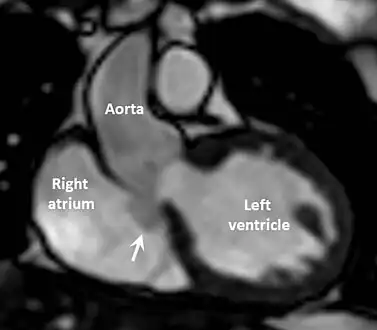

Diagnostic methodEchocardiogram, cardiac CT scan, cardiac MRI scan

Aneurysm of the aortic sinus, also known as the sinus of Valsalva, is a rare abnormality of the aorta, the largest artery in the body. The aorta normally has three small pouches that sit directly above the aortic valve (the sinuses of Valsalva), and an aneurysm of one of these sinuses is a thin-walled swelling. Aneurysms may affect the right (65–85%), non-coronary (10–30%), or rarely the left (< 5%) coronary sinus.[1] These aneurysms may not cause any symptoms but if large can cause shortness of breath, palpitations or blackouts. Aortic sinus aneurysms can burst or rupture into adjacent cardiac chambers, which can lead to heart failure if untreated.

The manifestations appear depending on the site where the sinus has ruptured. For example, if the sinus ruptures in a low pressure area like the right atrium or right ventricle then a continuous type of murmur is heard. The murmur is located in the left parasternal region mainly confined to the lower sternum. It is also accompanied by a superficial thrill. A ruptured Sinus of Valsalva abscess represents a surgical emergency.

The first step in diagnosis is typically transthoracic echocardiography. However, if surgery is planned or if the standard echocardiogram lacks sufficient detail, then one or more additional studies are recommended. These studies include transesophageal echocardiography, 3D echocardiography, CT Angiography and aortic angiography.[4] Cardiac MRI may be another option.[2]